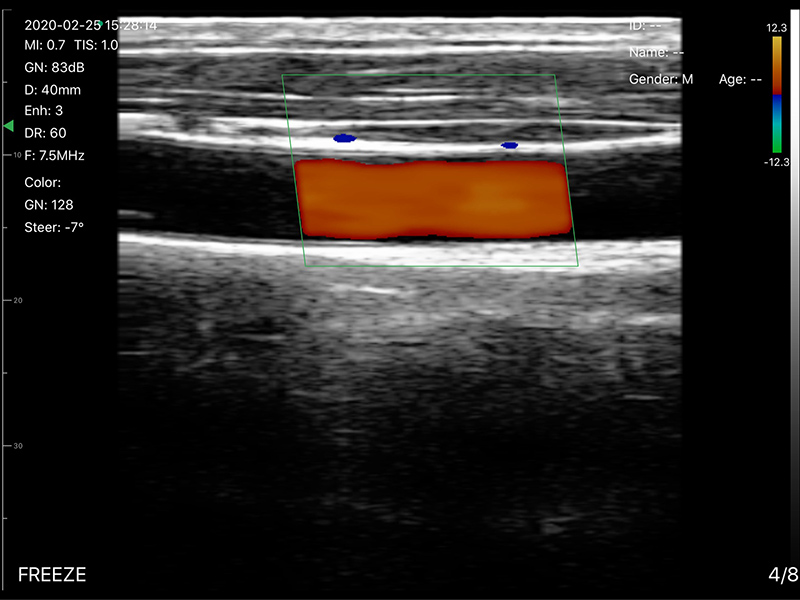

• 显示模式:B、B/M、Color、PW、PDI

• 探头频率:7.5/10MHz

• 扫描宽度:40mm